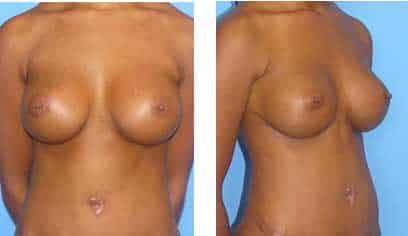

This patient presented to Dr. Agha for corrective breast augmentation. Her primary breast augmentation was performed by a non-plastic surgeon three years prior.

Both her breast implants were placed in a subglandular plane and were too low due to overzealous dissection of the inframammary fold.

Implant positions are asymmetrical, with the right implant lower than the left. She also had rippling of her right implant.

The patient underwent a corrective secondary breast augmentation procedure by Dr. Agha, as well as a tummy tuck.

A breast revision surgery involved removing the implants, reconstructing the lower inframammary fold, and placing silicone implants in a submuscular plane.